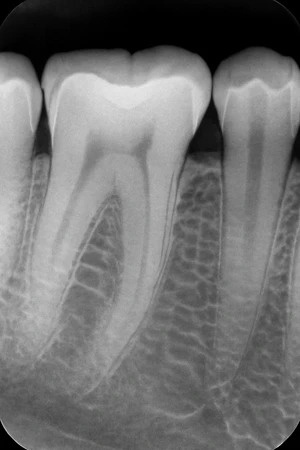

Pemeriksaan gigi dengan sinar X periapikal digital, untuk mendapatkan gambaran detail mengenai kondisi gigi dan struktur di sekitarnya.

Periapikal adalah jenis rontgen kecil yang dapat memberikan gambaran yang presisi pada 1-3 gigi yang bersebelahan. Rontgen gigi ini menggunakan sensor digital, maka hasil foto rontgen yang dihasilkan tampak lebih jelas.

- Menunjukkan panjang setiap gigi, dari mahkota hingga akar

- Melihat kondisi 1-3 gigi sebelum mengambil tindakan cabut gigi, perawatan saraf gigi, atau penambalan gigi

- Menemukan masalah gigi di bawah permukaan gusi atau dalam rahang, misalnya gigi bertubrukan, abses, kista, tumor, atau perubahan tulang akibat penyakit tertentu